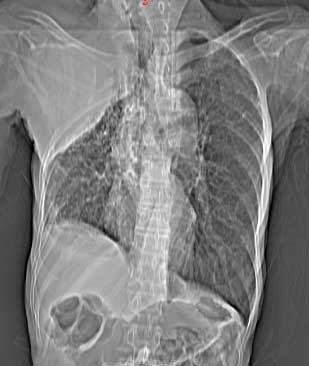

患者男,81岁,咳喘10余年,继往结核病史,发现胸部体表肿物(具体时间不详)就诊

右侧胸廓塌陷。右前上外侧胸壁软组织肿块,其内见有低密度影,肋骨呈溶骨性表现。右肺上叶见大量的间质纤维化表现。右侧膈肌上抬。

患者男,81岁,咳喘10余年,继往结核病史,发现胸部体表肿物

患者男,81岁,咳喘10余年,继往结核病史,发现胸部体表肿物。